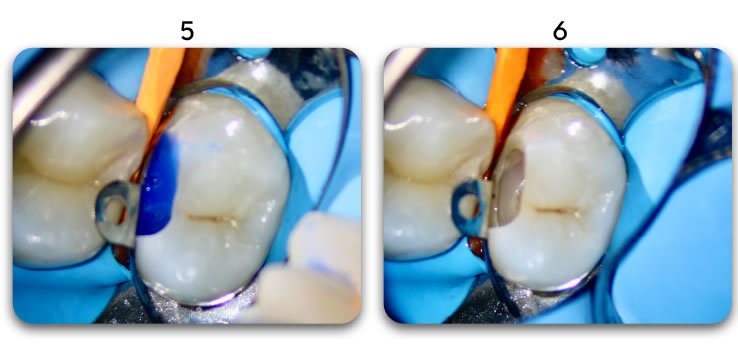

Excellent light transmission

Excellent light transmission for use with dual-cure resins, Biolight DUAL offer excellent light transmission through the optic fiber material.